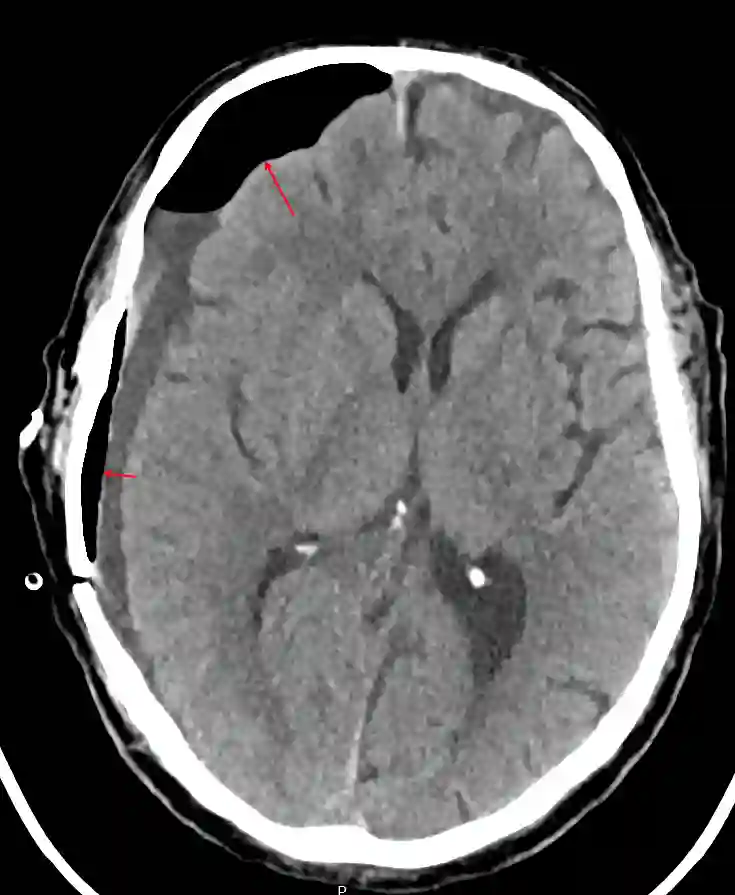

Die intrakraniellen Lufteinschlüsse lassen sich optimal in einer CT-Bildgebung als auch in einer MRT Bildgebung darstellen. Ein ausgeprägtes Pneumocephalus mit Kompression des Frontallappens kann sich in der CT-Bildgebung als sogenanntes Mount Fuji Zeichen darstellen.